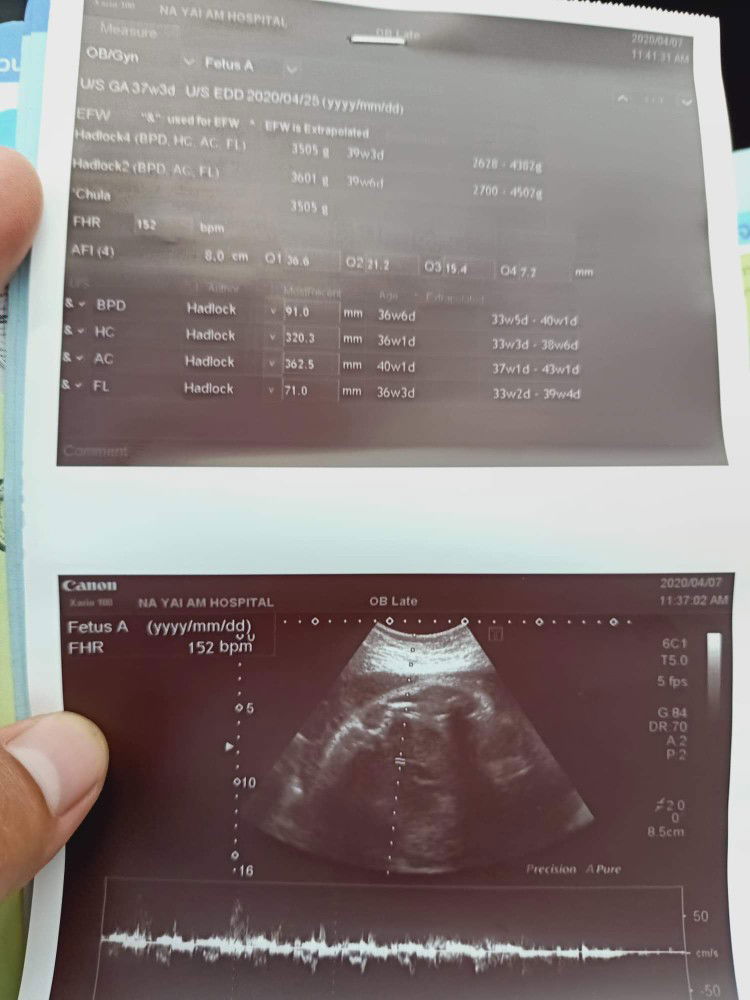

38w+5 มีน้ำไสๆไหล่ออกมาจากช่องคลอด

แม่ๆเคยเป็นมั้ยคะมีน้้ำไสๆออกจากช่องคลอด แต่ออกไม่เยอะออกทีละนิด ๆ แต่ไม่มีอาการปวดท้อง